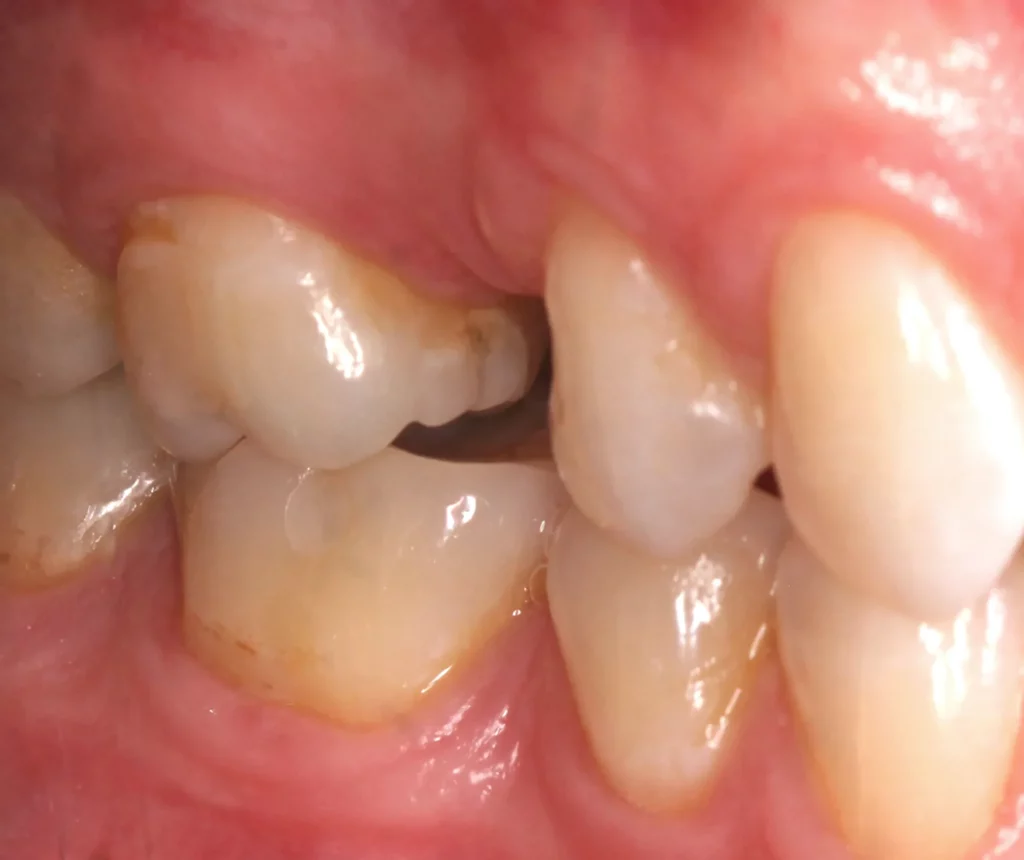

This woman had a badly broken down lower molar that had split apart and had been painfully abscessing for months. Unfortunately, it was beyond saving, and it was extracted. Keen to have the space restored, the patient opted to have an implant placed.

Below shows the crown fitted on to the implant post.